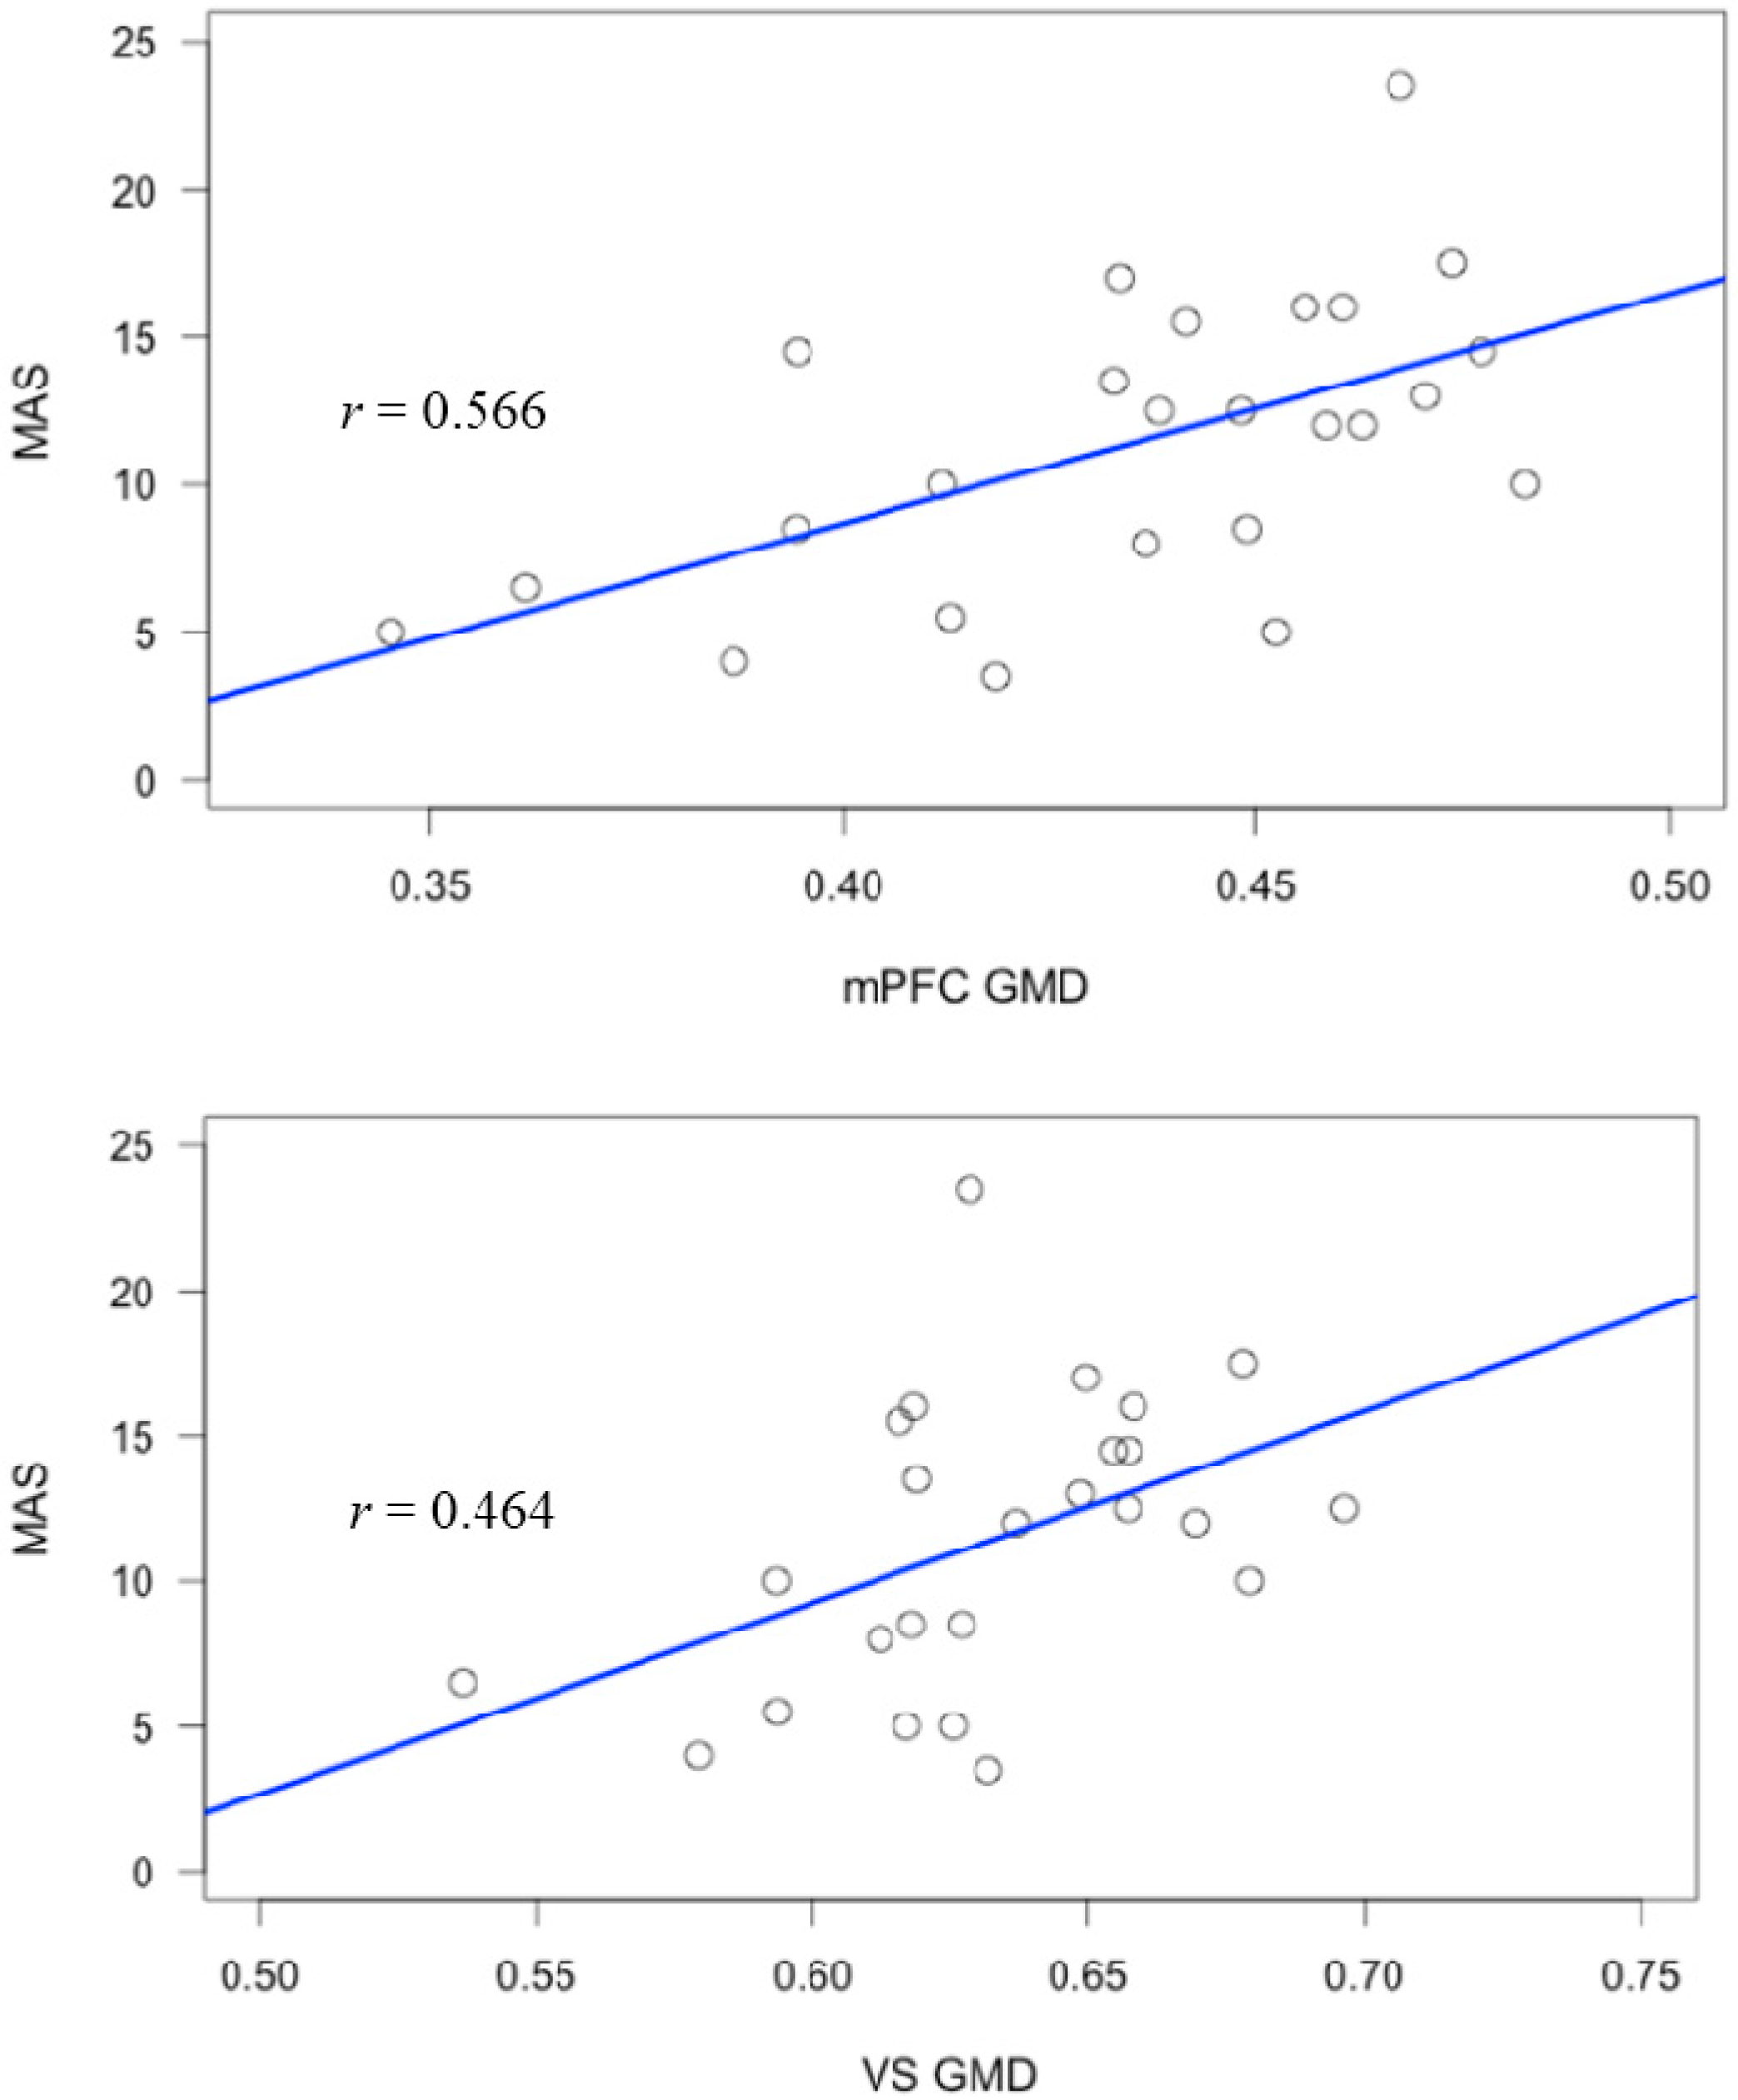

| Region | R/L | BA | MNI Coordinates (x, y, z) | t-Value (Peak Voxel) | Cluster Size (Voxels) |

|---|---|---|---|---|---|

| Medial prefrontal cortex | R | 9/10 | 18, 63, 7 | 4.07 | 2482 |

| Region | MAS-A | Self-Reflect | Other-Reflect | Mastery |

|---|---|---|---|---|

| mPFC | 0.566 ** | 0.605 ** | 0.424 * | 0.564 ** |

| VS | 0.464 * | 0.451 * | 0.367 | 0.513 ** |